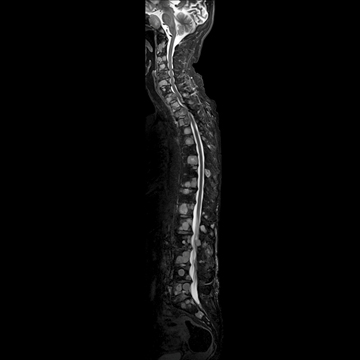

頚椎

T1 TSE, 384 matrix,

T2 TSE, 384 matrix,

T1 TIRM, 320 matrix,